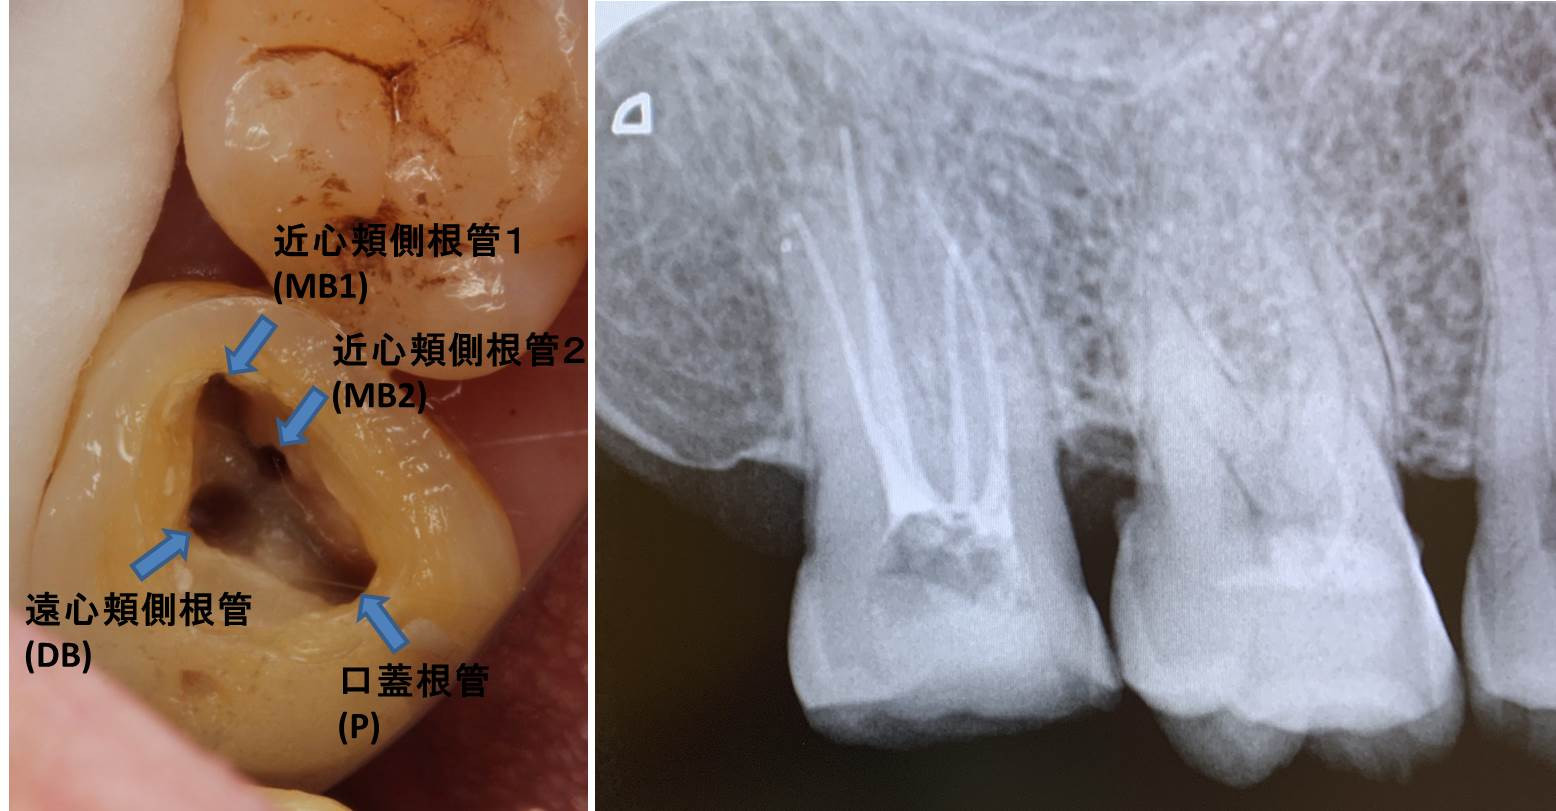

画像は右上7番の4根管症例で、全ての根管が狭窄・閉塞根管でしたが、なんとか根管充填まで処置完了し、数カ月の経過観察を挟んで予後良好と判断され、ようやく補綴処置、つまり被せる治療に移行となりました。

根の先が直接見えない根管治療においては画像診断歯科用顕微鏡が活躍します。当院では、3次元断層撮影のできる歯科用CTを完備しており、複雑な根の解剖学的な構造を診断することが出来ます。また、マイクロスコープを導入しておりますので、最大40倍拡大で根管の中を見ながら治療を進めます。